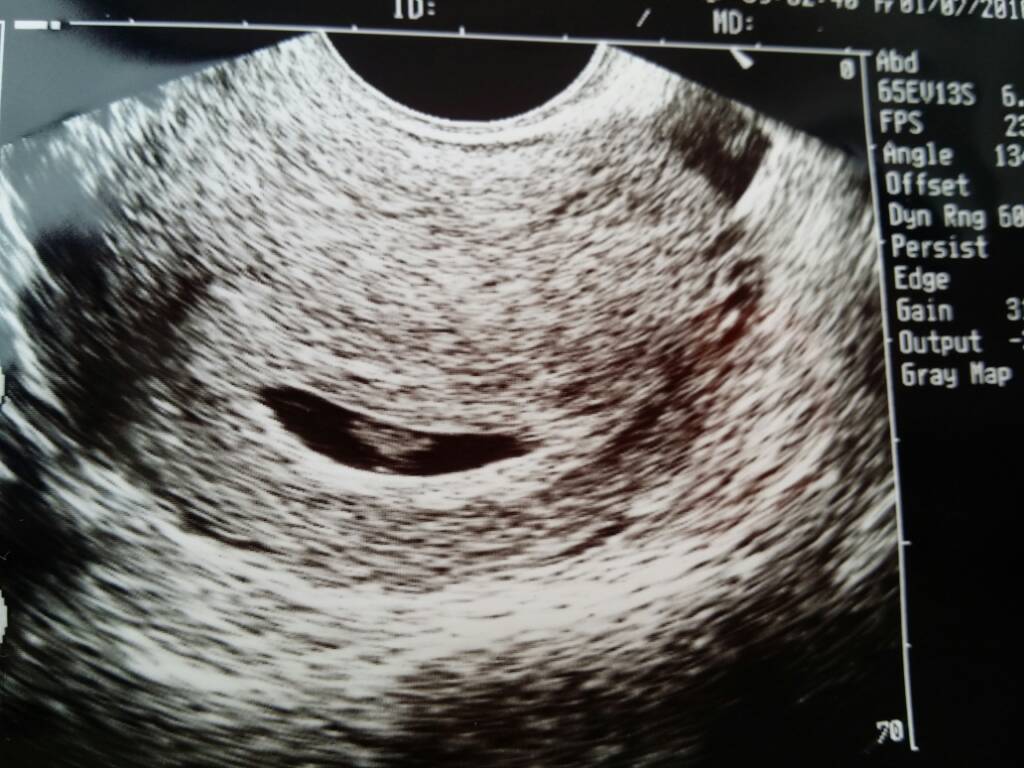

Ja po wizycie. Dobre wieści takie,że jest obywatel z bijącym serduszkiem. Złe: jest krwiak i stąd to plamienie z soboty. Mam luteine i nakaz oszczędzania. Postanowiliśmy z M powiedzieć o ciąży rodzinie to mi ktoś trochę przy Ali pomoże. Lekarz badał delikatnie a i tak plamie lekko.

1467365877-1d1mld.jpeg